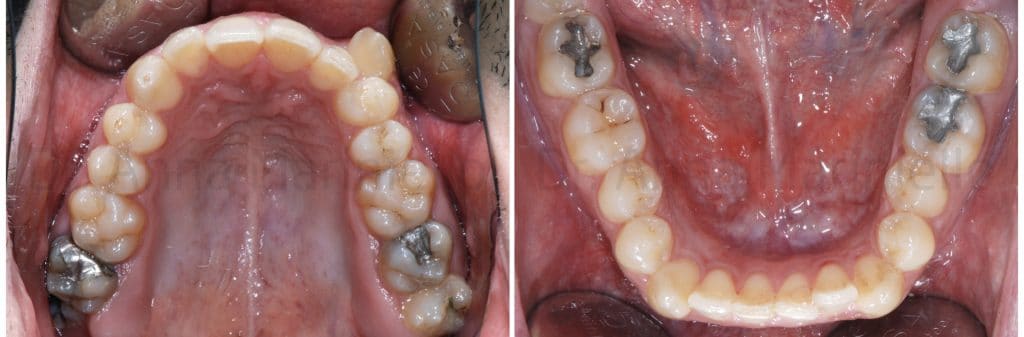

Considering the crowding amount in the upper arch we thought to an extraction treatment for the recovery of 23 space.

We chose to extract tooth 27 instead of 24 because it was compromised by a previous root canal therapy and had a great amalgam reconstruction.